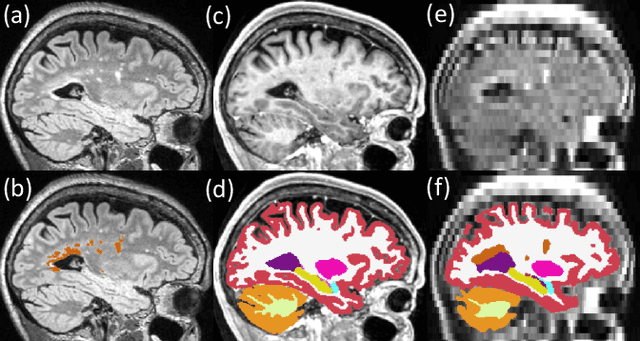

Abstract:Brain atrophy and white matter hyperintensity (WMH) are critical neuroimaging features for ascertaining brain injury in cerebrovascular disease and multiple sclerosis. Automated segmentation and quantification is desirable but existing methods require high-resolution MRI with good signal-to-noise ratio (SNR). This precludes application to clinical and low-field portable MRI (pMRI) scans, thus hampering large-scale tracking of atrophy and WMH progression, especially in underserved areas where pMRI has huge potential. Here we present a method that segments white matter hyperintensity and 36 brain regions from scans of any resolution and contrast (including pMRI) without retraining. We show results on six public datasets and on a private dataset with paired high- and low-field scans (3T and 64mT), where we attain strong correlation between the WMH ($\rho$=.85) and hippocampal volumes (r=.89) estimated at both fields. Our method is publicly available as part of FreeSurfer, at: http://surfer.nmr.mgh.harvard.edu/fswiki/WMH-SynthSeg.